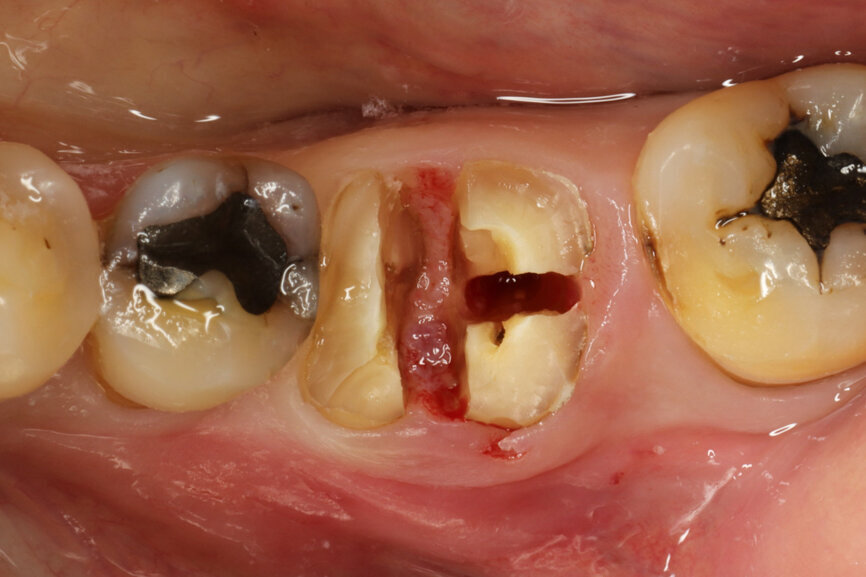

Fig. 4: Root splitting for minimally traumatic extraction.

Fig. 5: Socket dimensions preserved.

The surgical procedure was carried out under conscious sedation with local anaesthetic, and routine sterile preparations for surgical procedures were followed. To preserve the gingival and surrounding walls as far as possible, a flapless minimally traumatic approach to the extraction was employed by splitting the roots in different directions (Fig. 4). Extra precautions were taken not to inflict any trauma, not even by the suction device on the papilla and any surrounding soft tissue. A simple orthodontic elastic was placed around the adjacent teeth to delimitate the buccal and lingual red zone margins that should not be encroached upon.

It was possible to verify solid interradicular bone availability (Fig. 5), extending further the limits of the root apices and allowing for a centrally oriented osteotomy. The implant bed preparation started with the use of a needle drill at 800 rpm, followed by the ⌀ 2.2 mm and ⌀ 2.8 mm drills (Figs. 6–10). The implant was placed with the use of ratchet and torque control, reaching the desired final position at a 50 N cm torque value (Figs. 11–13). The socket was then augmented with bovine-derived bone substitute impregnated with advanced platelet-rich fibrin (A-PRF) and finalised with sutures to keep the A-PRF application immobile, and a 3 mm healing abutment was placed (Figs. 14–17).